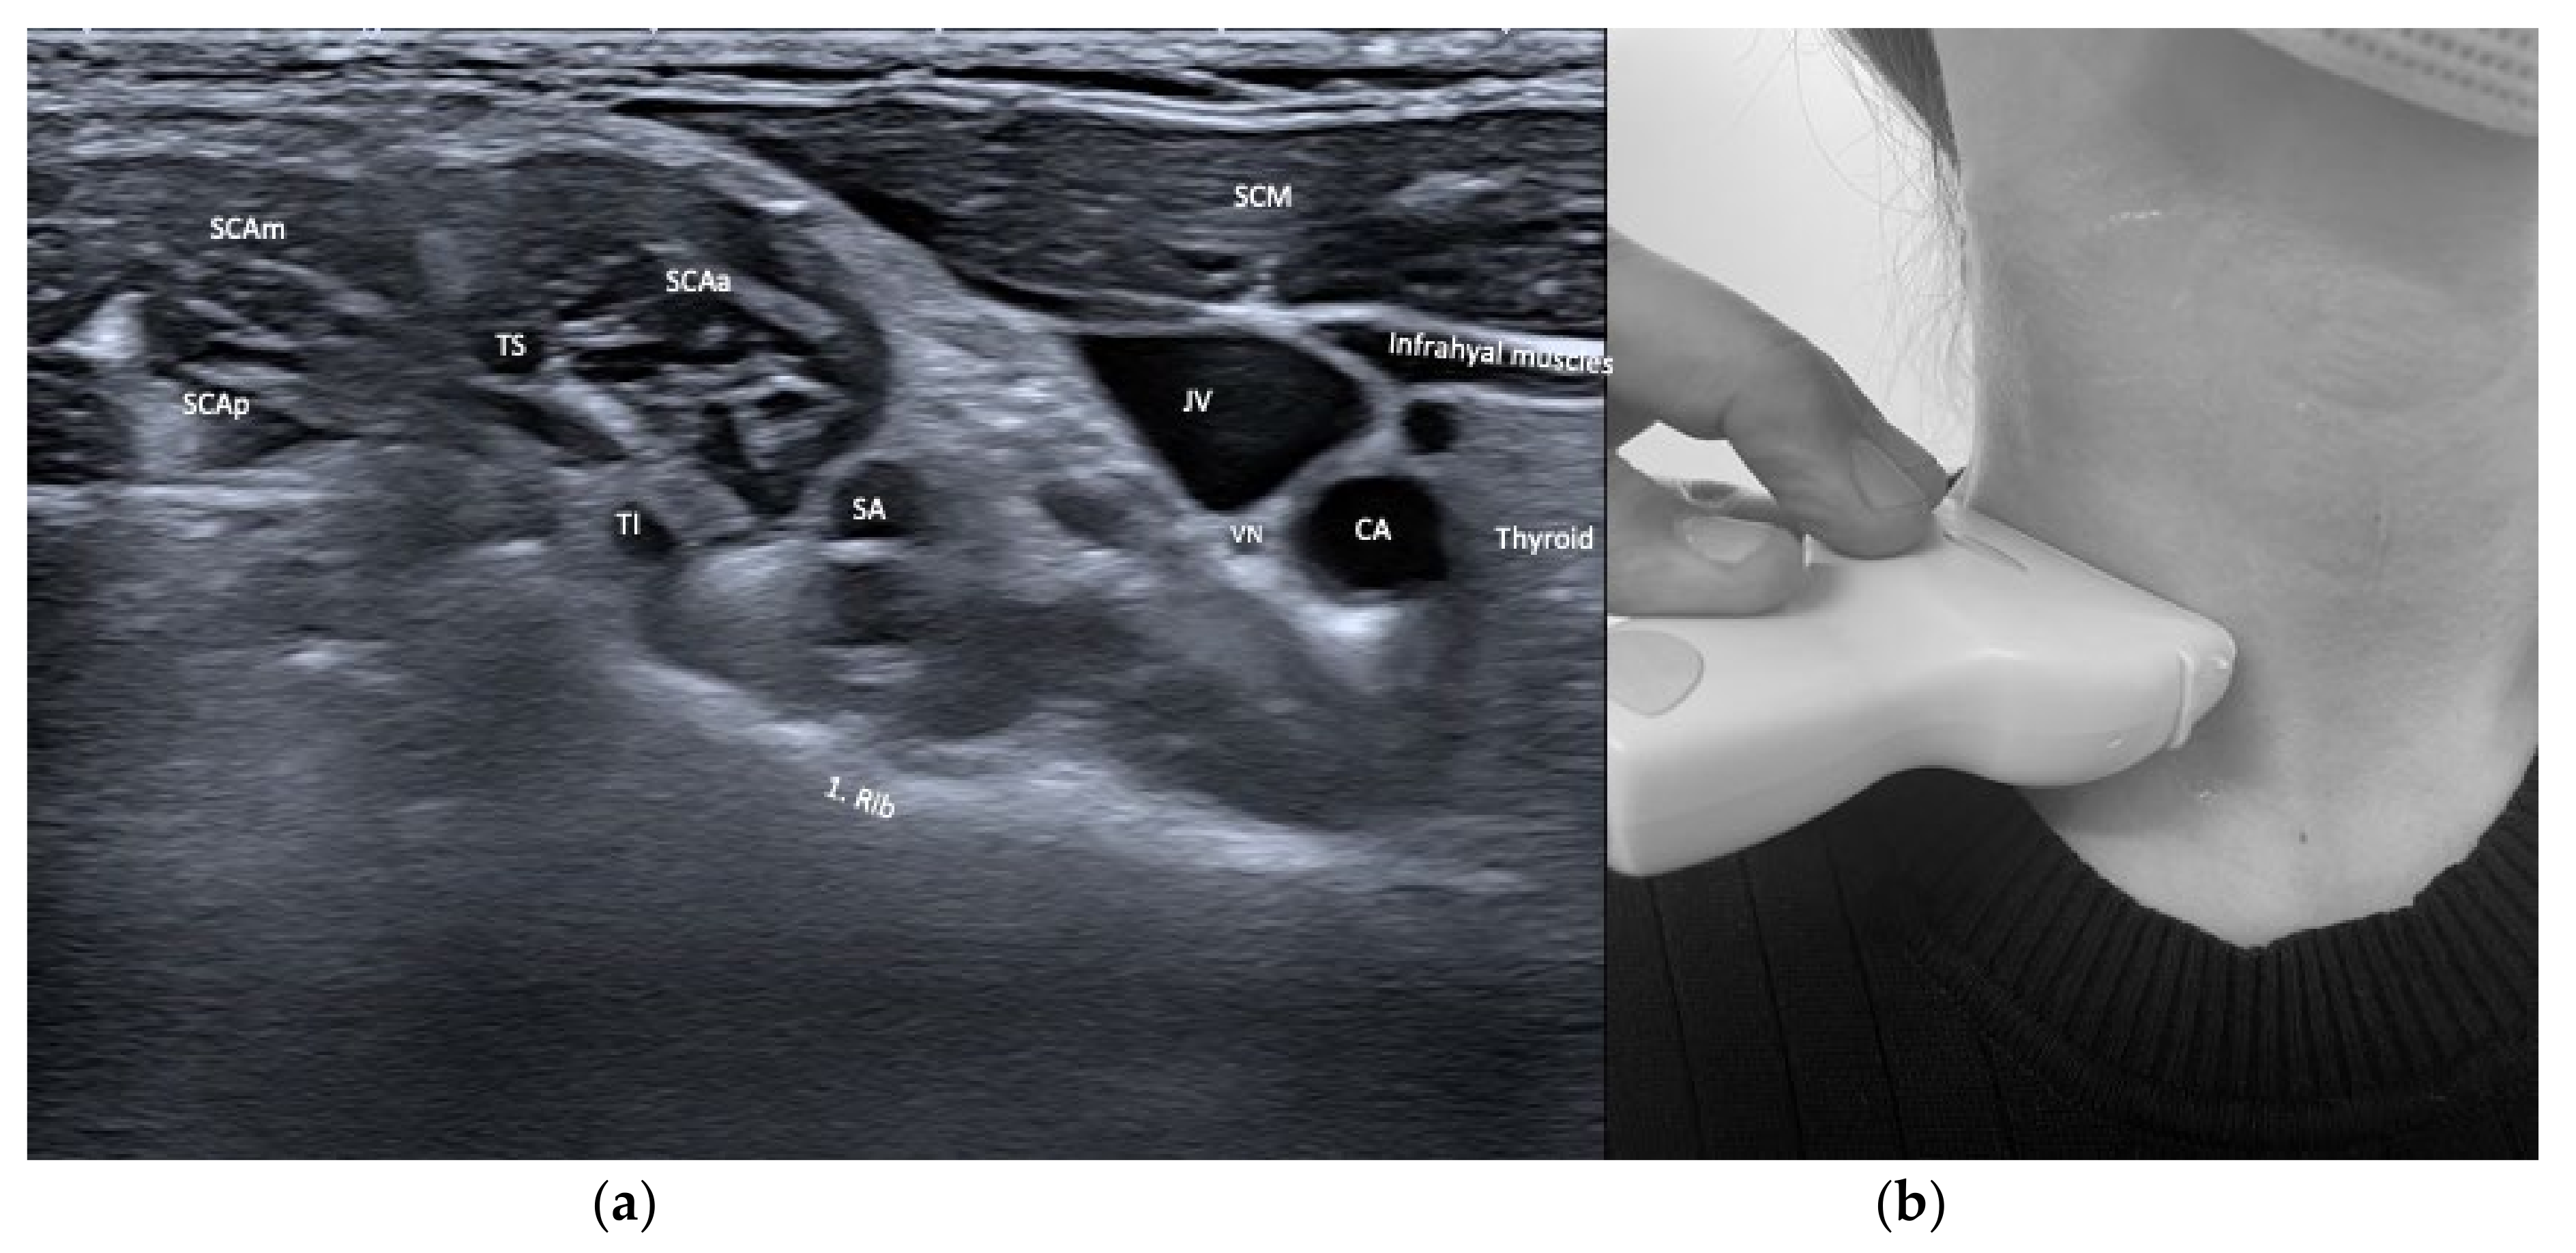

3.4. Safety Issues and Imaging of Relevant Neighboring Structures

| Scalenus anterior (SCAa) | Anteflexion of neck | +++ | +++ | Thyroid, carotid artery, brachial plexus, phrenic nerve, lung | |

| Scalenus medius/posterior (SCAmp) | Ipsitilt of neck | ++ | ++ | Brachial plexus, lung | |